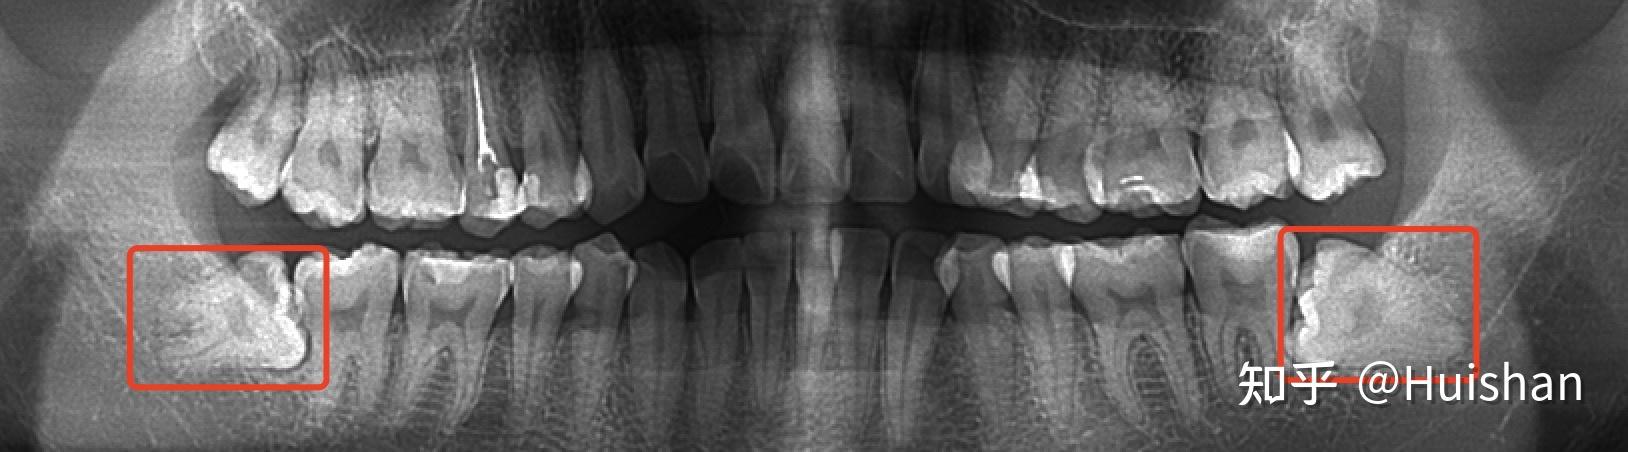

阻生智齿

智齿拍片